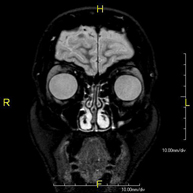

- Brain MRI (cranial)

This non-invasive diagnostic procedure uses an electromagnetic field and radio waves (from a transmitter and receiver) to acquire high-definition anatomical images of the brain. It is a radiation-free procedure. Indicated for: vascular problems, memory loss, epilepsy, headache, malformations, suspected tumour, meningitis.